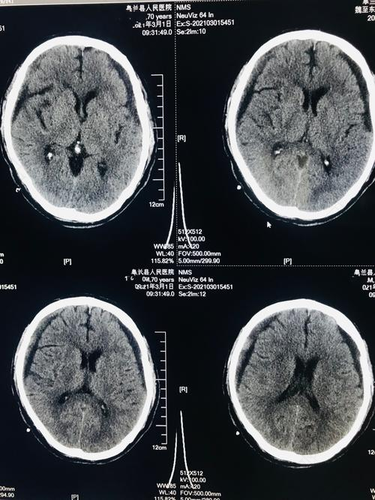

每个人都知道大脑在人体中的重要地位,因此谁也不敢小觑。不管是工作还是学习都是会用到大脑的,所以大家也对大脑格外的关心,脑壳出血可是相当严重的一件事,严重的会危及生命。那么硬脑膜下出血怎么办?